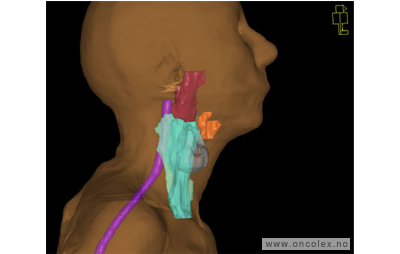

Skisse over hvordan strålefeltet planlegges:

Illustrasjon for målvolum

• GTV (Gross Tumor Volume): Identifisert tumor.

• CTV (Clinical Target Volume) GTV + omkringliggende vev hvor det kan væremikroskopisk spredning.

• ITV (Internal Target Volume): CTV + en indre margin som tar hensyn tilindre bevegelser og endringer av CTV.

• PTV (Planning Target Volume): Innstillingsmargin som inneholder ITV og samtidig tar hensyn til antatte pasientbevegelser, samt variasjoner i pasientopplegging og feltinnstillinger.

• Feltgrense. Tegnes som oftest på kroppen.

ICRU (International Commission on Radiation Units and Measurements)